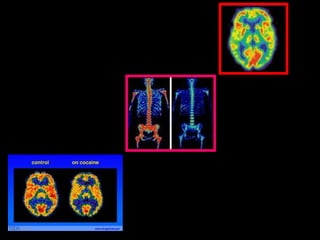

PET imaging

• Positron Emission Tomography

– Nuclear Medicine

• Use trace amount of radioactive material

(radiopharmaceuticals or radiotracers) to

diagnose and depict a disease

– Cancer

– Heart Disease

– Gastrointestinal diseases

• Nuclear medicine accurately

pinpoints molecular activity within

the body

How it Works

• Radiotracers are injected,

swallowed, or inhaled as a gas

• Accumulate in the organ/area being

examined

• Radiotracers give off energy called

a gamma ray

• Then a gamma camera, PET scanner, or

probe detects this energy and

converts it into a picture with the

assistance of a computer